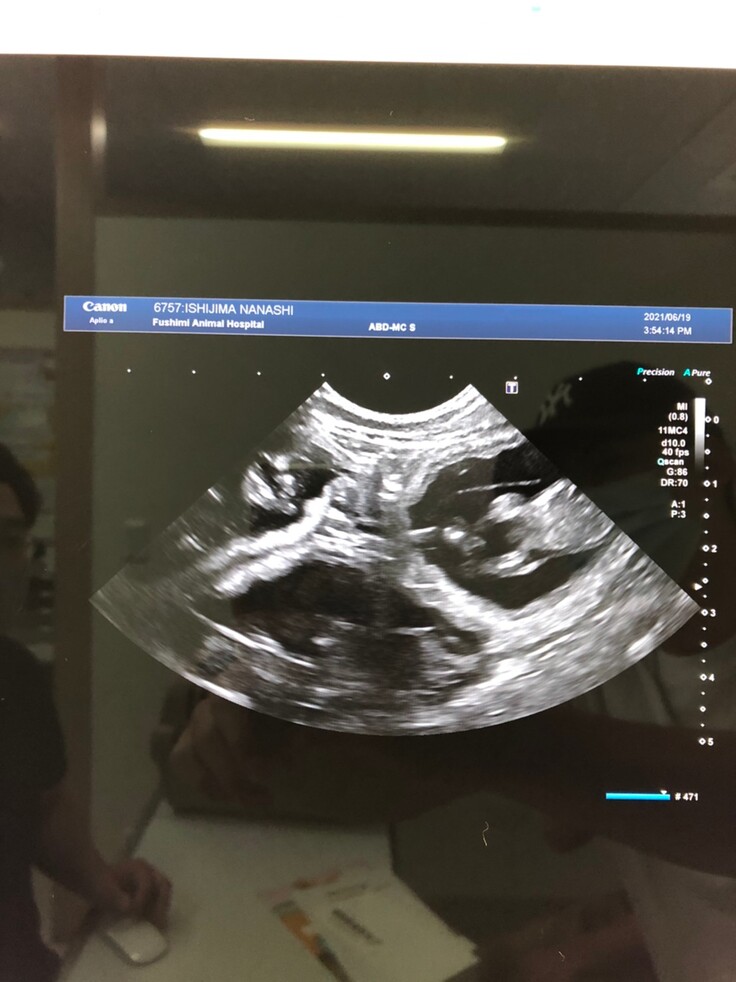

動物病院で診てもらったところ2箇所骨折している事がわかりました。幸いにも内臓には大きな怪我がなかったので、5日間入院して整形外科対応病院に転院しました。

検査で妊娠していた事が発覚したレントゲン